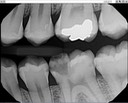

Scott Kanamori #12 pre-op